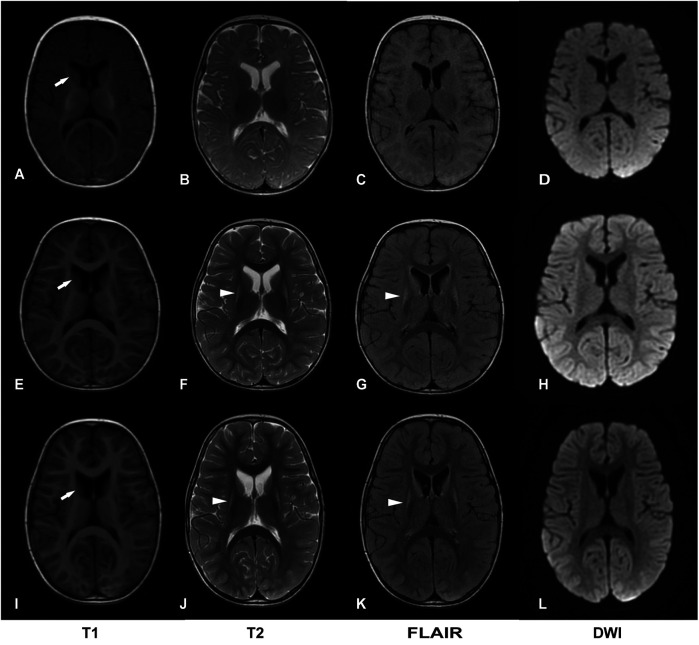

Case presentation: We report a third case of Leigh syndrome associated with MRPS36 variants in a 2-year-old boy. The patient exhibited with global developmental delay, dystonia, early-onset chorea, and elevated serum lactate levels. Follow-up brain magnetic resonance imaging at 2 years revealed progressive degenerative lesions in the bilateral basal ganglia. Muscle biopsy showed abnormal mitochondrial accumulation beneath the sarcolemma, and the oxygen consumption rate was reduced in skin fibroblasts. Whole-exome sequencing identified two novel compound heterozygous MRPS36 variants: c.42+1G>A (p.?) and c.296G>C (p.Arg99Pro).